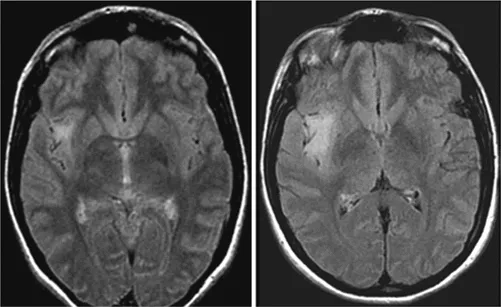

神经节神经胶质瘤(WHO I级)是最常见的致癫痫性肿瘤,尽管它仅占所有脑肿瘤的1%至4%。它往往发生于具有长期药物难治性癫痫病史的儿童和年轻人中。复杂部分性发作最为常见。尽管神经节神经胶质瘤倾向于出现在颞叶,但它可发生在神经轴的任何部位,包括颈髓连接处、松果体区和鞍上区域。颞叶外的位置与组织学异型性和间变性相关(间变性神经节神经胶质瘤;手术是这些肿瘤的主要治疗手段[见图3])。虽然有报道称存在恶性转化可能,但其通常是良性的。幕上神经节神经胶质瘤通常可以实现手术全切,因此是可治愈的,并为约80%的患者带来了Engel I级(无癫痫发作)的结局。为了进一步改善癫痫发作的控制,建议进行脑病灶切除联合邻近颞叶新皮质切除术。实现肿瘤全切的主要障碍是肿瘤的中线位置(如脑干),其他限制因素包括肿瘤边界不清、靠近重要功能皮层以及浸润了关键结构。

图3。一名11岁患儿,右颞部肿瘤表现为多发囊肿并伴有明显强化的实性瘤体部分。术前与术后轴位T1加权磁共振成像对比,提示肿瘤被完全切除,最终病理诊断为神经节神经胶质瘤。